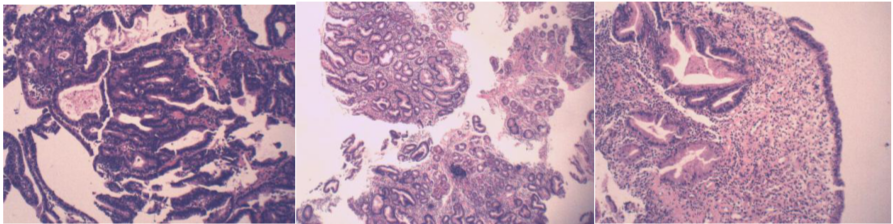

2018-3-14经皮肝穿病理:符合胃癌并肝转移。

病理示:(肝)癌。

免疫组化结果:Glypican-3(-),Hepatocyte(-)不支持肝细胞癌,NapsinA(-),TTF-1(-),不支持肺癌转移;CEA(+),CK(+),CK19(+),CK20(-)CK7(+)。

(胃)中-低分化腺癌,取材浅,组织碎,未知深部浸润情况;

免疫组化:P21(-/+),CEA(+),P53(+),Ki67阳性率约为60%,D2-40(-),HER2(2+);

HER2荧光原位杂交检测结果判读:HER2基因有扩增